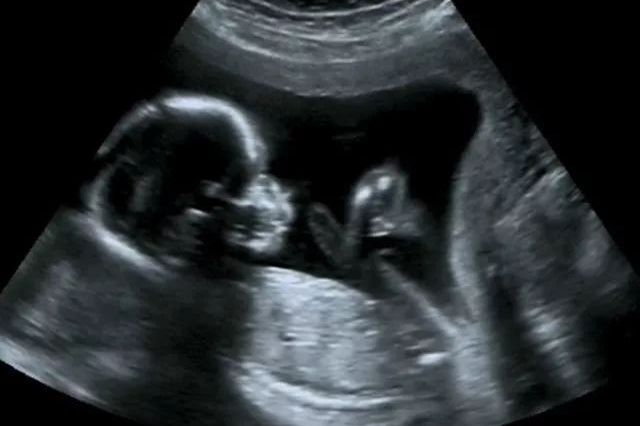

胎儿查出多囊肾,能要吗?

多囊肾为一种常见的家族遗传性疾病,是一种先天性肾发育异常的疾病,其病理改变是两侧肾实质内发生无数个潴留性囊肿,可分为常染色体显形遗传的成人型和常染色体隐性遗传的婴儿型。 高血压是多囊肾最常见的早期表…